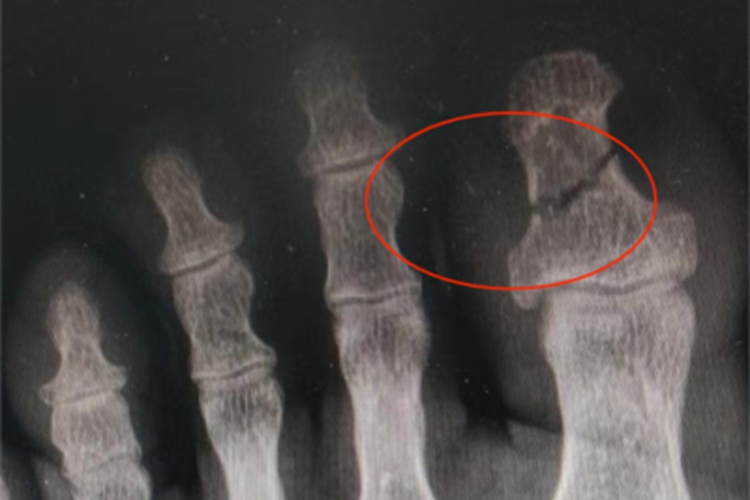

- 骨折愈合大致可以分为四个阶段,血肿机化期、原始骨痂形成期、骨痂改造塑形期和骨痂成熟愈合期。在血肿机化期,骨折断端周围的血肿会逐渐被肉芽组织所取代,紧着原始骨痂形成期,成骨细胞和破骨细胞活跃,开始在骨折两端形成骨痂,逐渐连接起断裂的骨骼。

- 随着时间的推移,进入骨痂改造塑形期,骨骼内部的骨小梁结构会根据力学需要进行重新排列,使骨折部位逐渐恢复到接近正常骨骼的强度和形态,在骨痂成熟愈合期,骨折线完全消失,骨骼恢复至完全愈合状态,恢复其原有的承重和运动功能。